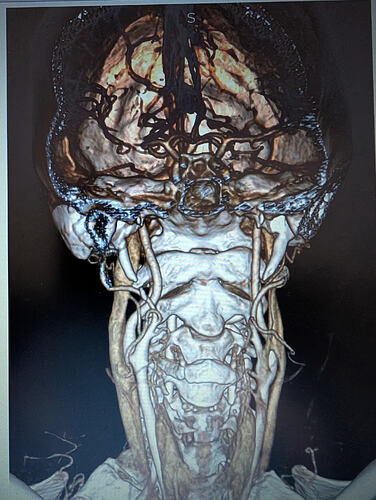

I have edited my post one more time, it must be my anxiety. I have added a picture of my scan with contrast. My elongated styloid processes are trapping my jugular vein. My carotid artery is off track… :scream:

@Hamela - Your styloids aren’t terribly long, but they are exceedingly thick, especially the left one which is a bit more angled than the right one. The right one is more curved. The thickness & angles of growth can significantly play into the symptoms & compression the styloids are causing.

Due to your bilateral IJV compression, it would be best for you to contact Dr. Costantino or Dr. Cognetti for help as they are the two doctors closest to you who do styloidectomies w/ IJV decompression.